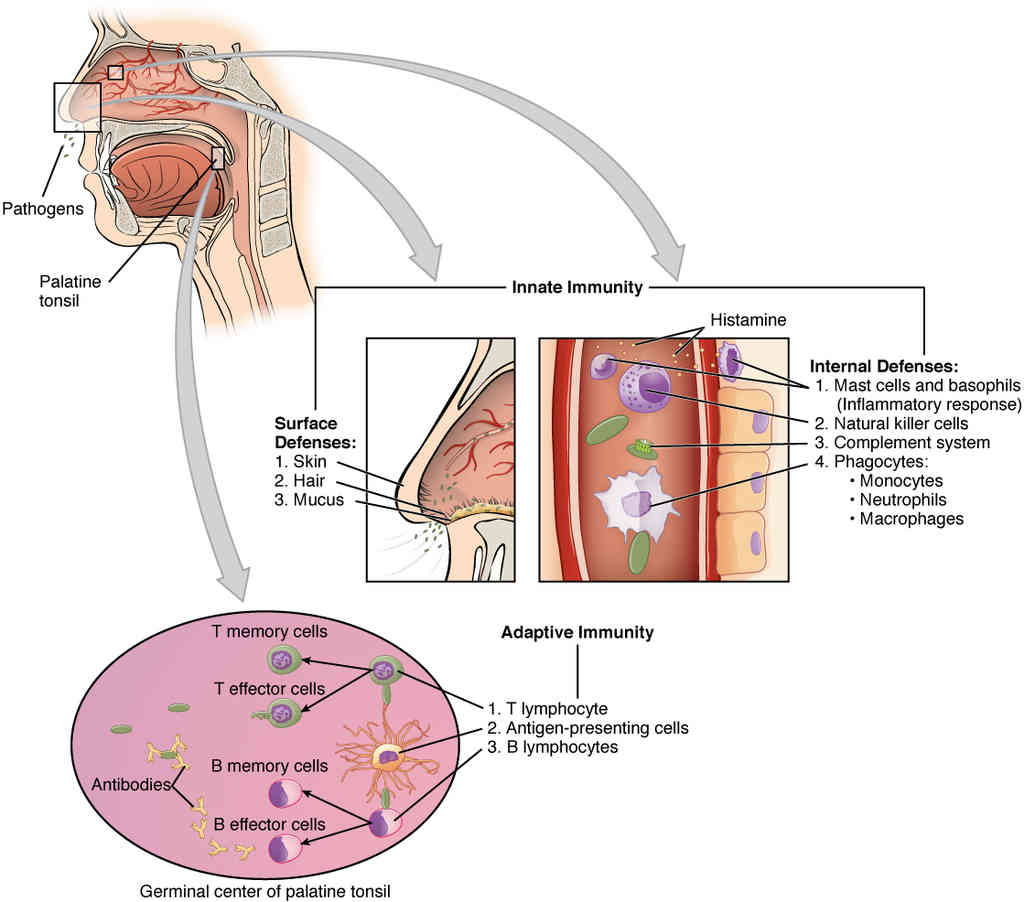

This page is under construction. For now, it is just a resource of the images found in the OpenStax Anatomy and Physiology Handbook. It wil slowly change into a revision tool. Each slide has a number. Use this to refer to the slide. When completed, it will have an unlabelled section, with labelled slides in parallel. On the unlabelled slides, write your answer and use the labelled slide to assess yourself. Keep track by also noting the number on each slide. Improvement at each attempt is important, more so than full marks on a first attempt.